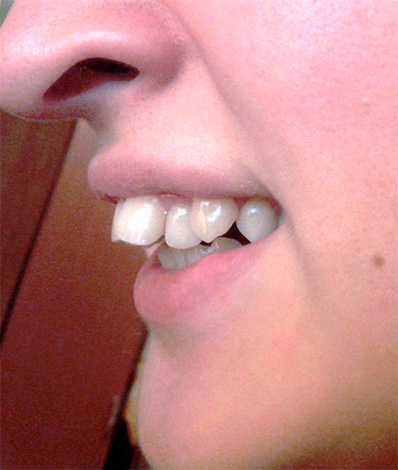

Morso incrociato

Come suggerisce il nome, con un morso incrociato, i denti, chiudendosi, si intersecano.

Con un morso incrociato, c'è una discrepanza nella dimensione delle mascelle nella regione laterale. Gli ortodontisti attribuiscono questo tipo di occlusione a anomalie trasversali e la patologia può essere unilaterale e bilaterale.